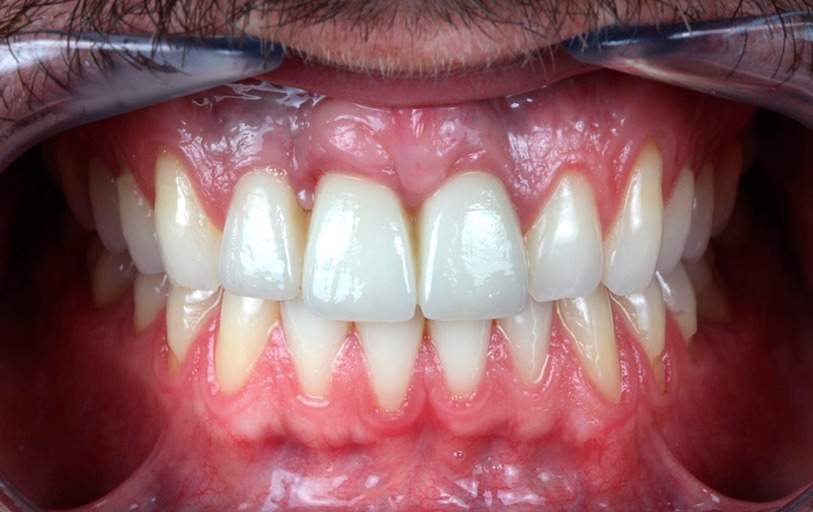

Ortodoncia

BeforeAfter